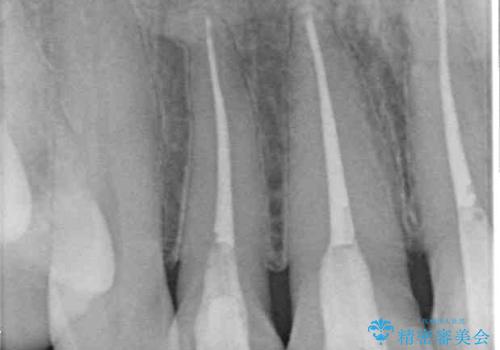

- 上顎4前歯に装着されているセラミッククラウンのうち、ひとつが欠けてしまったとのことで来院された患者様です。

土台となっている歯には問題がないため、周囲のセラミッククラウンと色調が合うように、オーダーメイドタイプのセラミッククラウンにて補綴治療を行うこととしました.

欠けてしまったセラミッククラウンはガラス系セラミッククラウンであったため、今回製作する歯は、強度の強いジルコニアセラミッククラウンとしました。

クラウンの種類は異なりますが、色調の適合したクラウンを装着することができました。